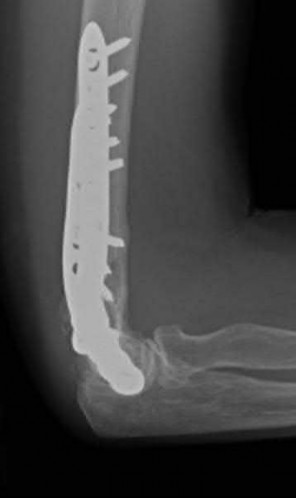

Question 3:

A 15-year-old boy presents with a permeative lytic lesion in the femoral diaphysis with aggressive periosteal reaction ('onion skinning'). Biopsy reveals uniform small round blue cells. Cytogenetic analysis of this tumor will most likely demonstrate which of the following translocations?

Correct Answer: t(11;22)

Explanation:

The clinical and radiographic description is classic for Ewing sarcoma. The characteristic cytogenetic abnormality is a balanced translocation t(11;22)(q24;q12), which fuses the EWS gene on chromosome 22 with the FLI1 gene on chromosome 11. This is seen in approximately 85-90% of Ewing sarcomas. t(9;22) is the Philadelphia chromosome (CML), t(X;18) is seen in synovial sarcoma, t(2;13) in alveolar rhabdomyosarcoma, and t(12;16) in myxoid liposarcoma.